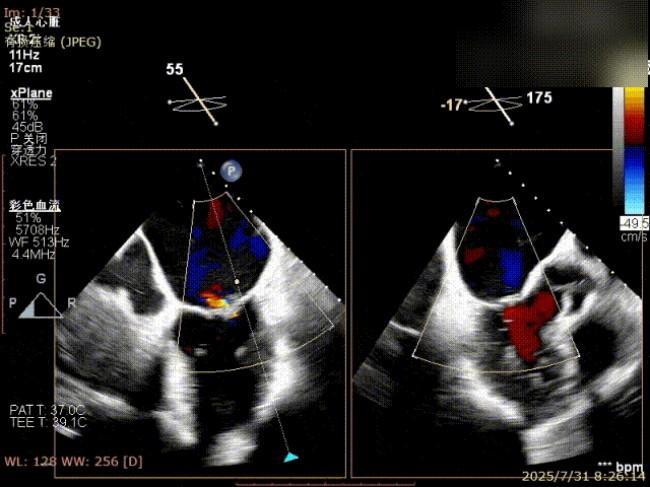

房间隔穿刺

夹合器“一字型”状态进入左房